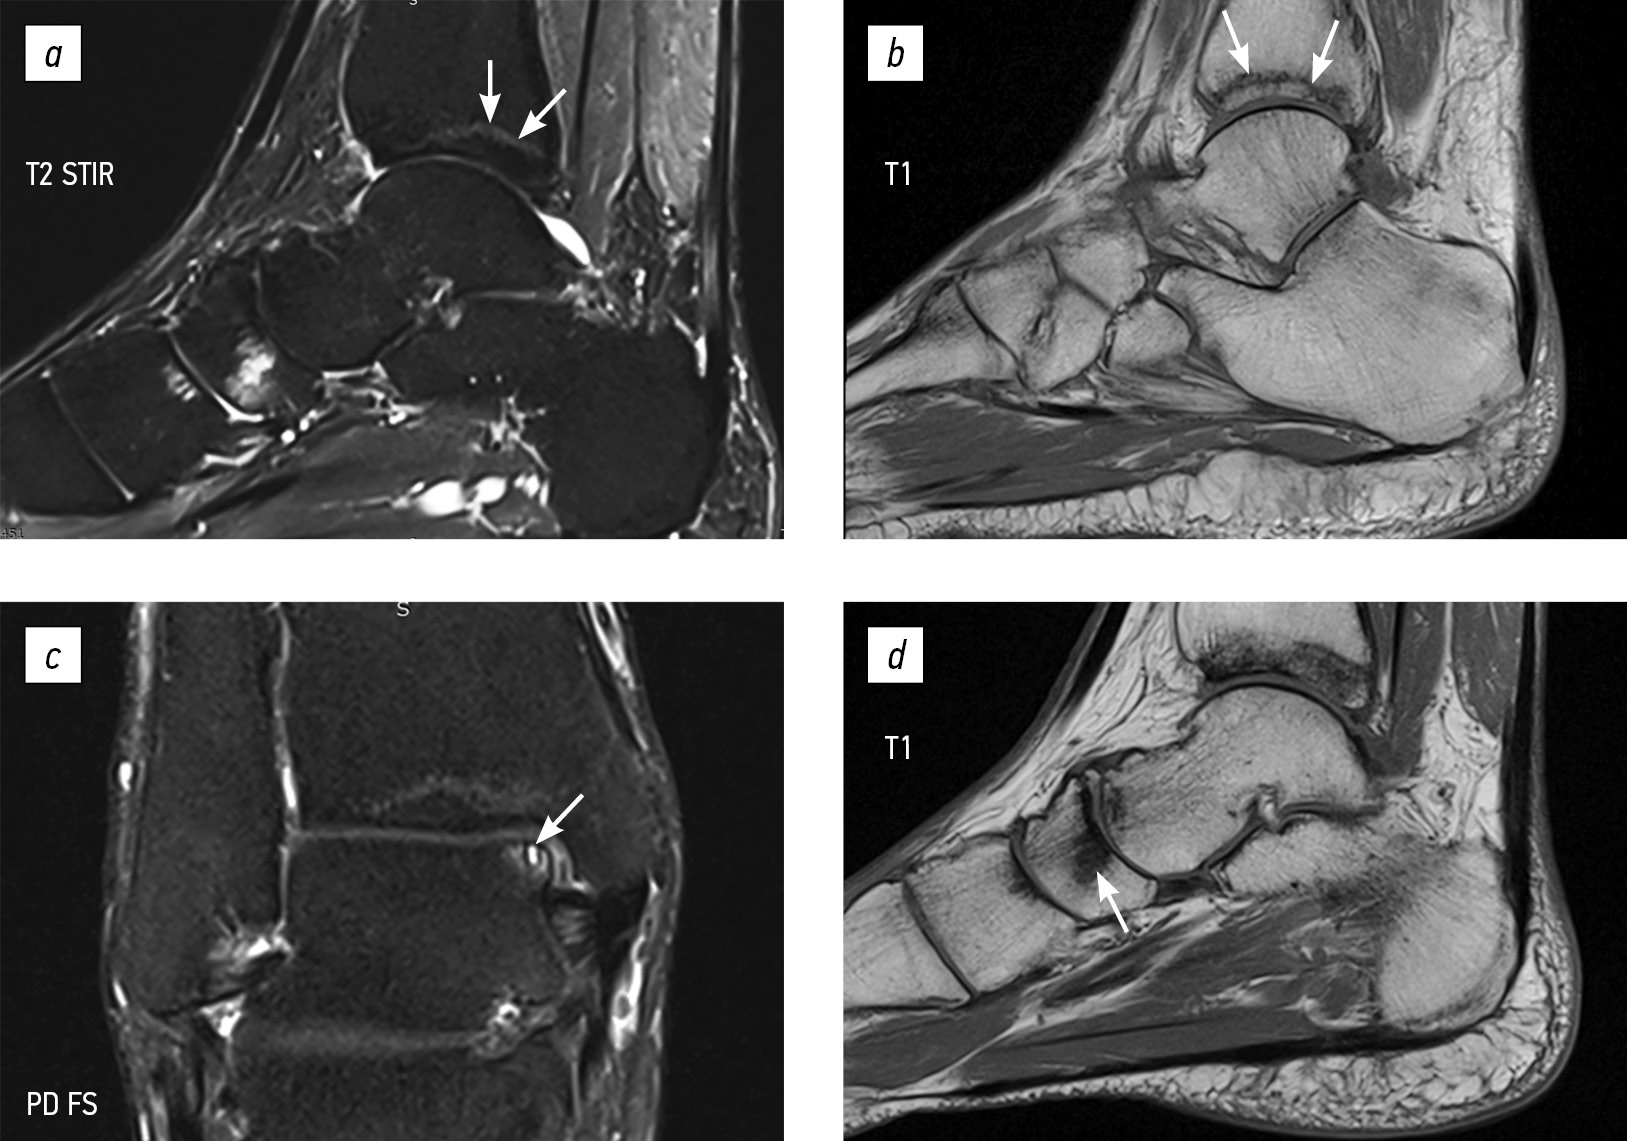

Проведено лабораторное исследование (декабрь 2023 г.): уровень креатинина крови составил 146,9 мкмоль/л, активность щелочной фосфатазы — 216 Ед/л, уровень фосфора — 0,7 ммоль/л (при норме 0,81–1,45 ммоль/л). В моче: уровень фосфора был 8,6 ммоль/л, креатинина — 4,79 ммоль/л. Расчетная канальцевая реабсорбция фосфора составила 62% (при норме 85–95%), соотношение максимальной реабсорбции фосфатов и скорости клубочковой фильтрации — 0,44 ммоль/л (при норме 0,84–1,23 ммоль/л). Концентрация ФРФ-23 составила 19,863 пг/мл (умеренное повышение). При рентгенографии стоп в двух проекциях заподозрен асептический некроз таранных костей, преимущественно справа (рис. 1).

Рис. 1. Боковая (а) и переднезадняя (b) рентгенограммы правого голеностопного сустава. Нарушение архитектоники таранной кости в виде неравномерного разрежения костной ткани (подозрение на асептический некроз). Сужение суставной щели голеностопного сустава.

Fig. 1. Lateral X-ray view (a) and frontal X-ray view (b) of the right ankle. Impaired architecture of the talus manifested by heterogeneous bone loss (suspected aseptic necrosis). Ankle joint space narrowing.